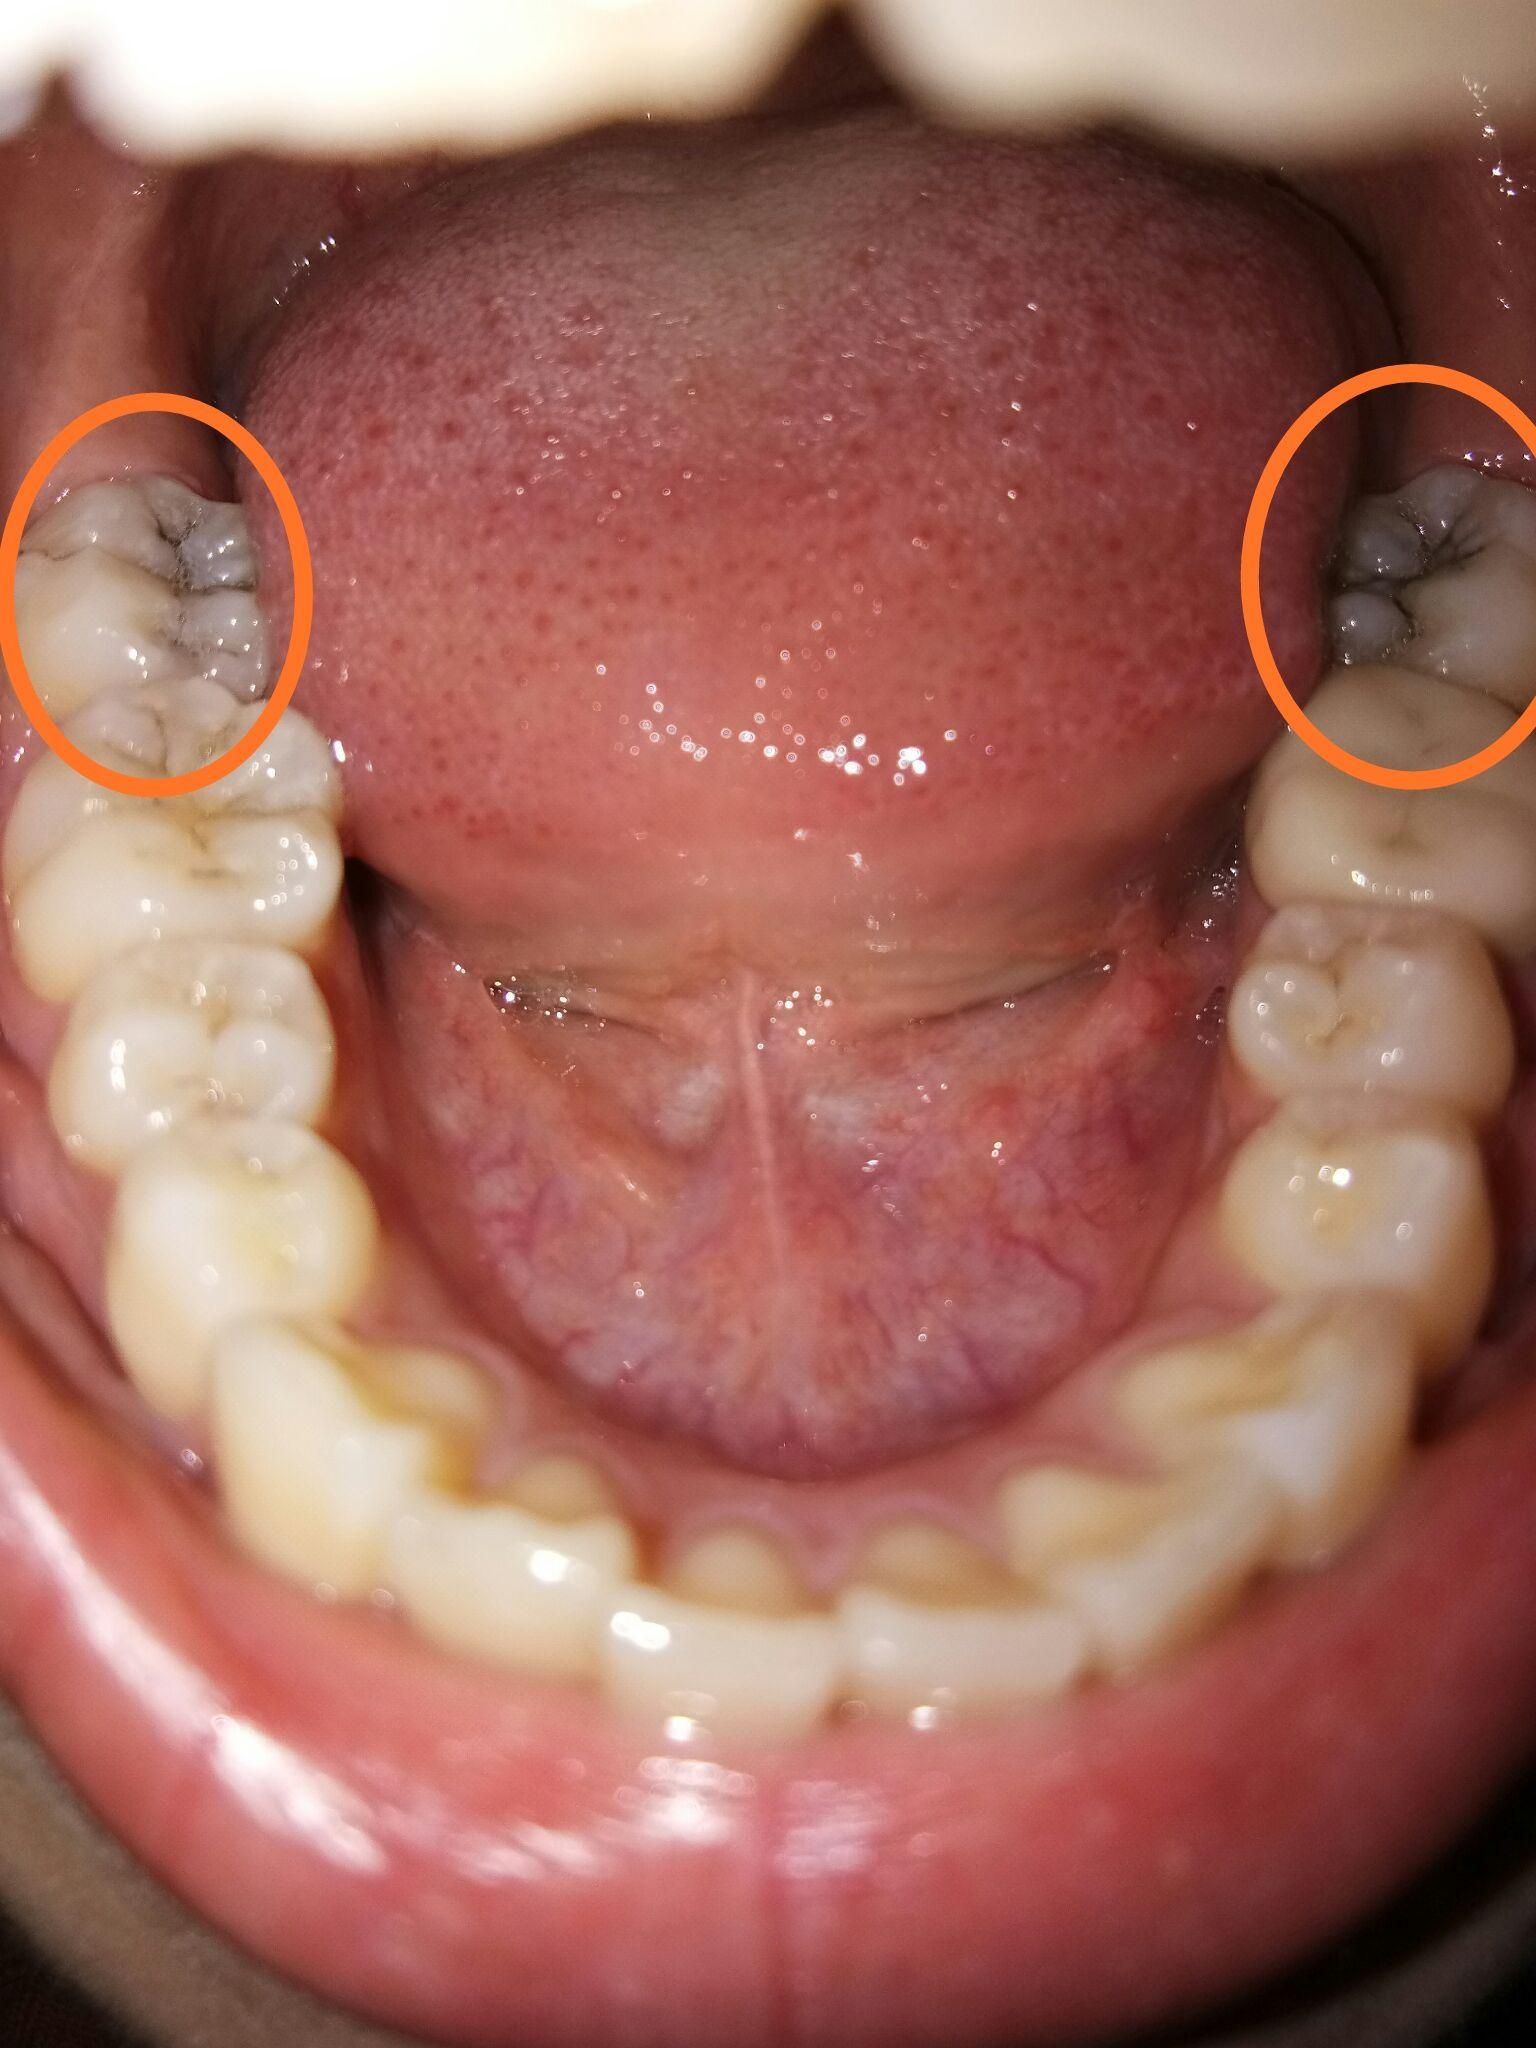

最后两颗大牙中间凹槽里是黑色的线,用针也挑不出

图片尺寸1200x1600

我这颗沟槽有黑丝的大牙是不是窝沟龋

图片尺寸600x600

牙齿咬合面上的黑线如何去除?

图片尺寸600x338

指不损伤牙体组织,将窝沟封闭材料涂布于牙冠咬合面,颊舌面的窝沟点隙

图片尺寸379x253